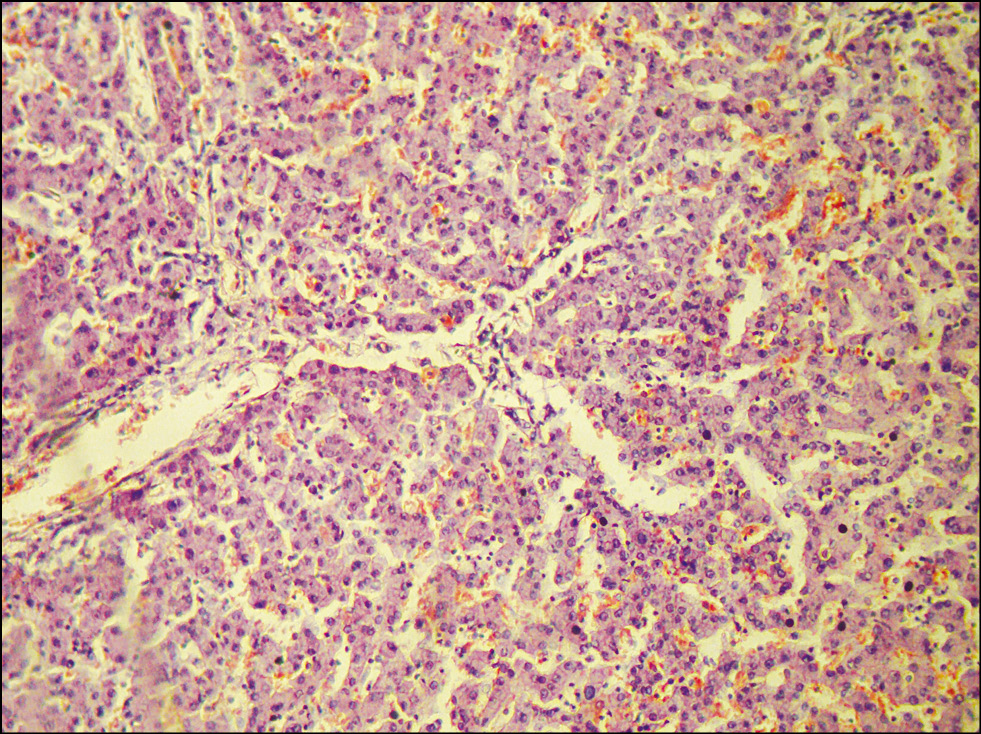

Микропрепарат кожи: некролиз большей части эпидермиса; в области дефекта кожи поверхностные слои дермы некротизированные; умеренная очаговая нейтрофильная и лимфоцитарная инфильтрация; полнокровие сосудов дермы (рис. 5).

Рис. 5. Микропрепарат кожи. Острый эпидермальный некролиз. Межклеточный и внутриклеточный отёк, выраженный ангиоматоз, воспалительный инфильтрат с примесью тучных клеток и эозинофилов. Нарушение межклеточных связей. Окраска гематоксилином и эозином. Ув. 250. / Fig. 5. Microslide of skin. Acute epidermal necrolysis. Intercellular and intracellular edema, pronounced angiomatosis, inflammatory infiltrate with an admixture of mast cells and eosinophils. Violation of intercellular communications. Staining with hematoxylin and eosin. Magnification 250.